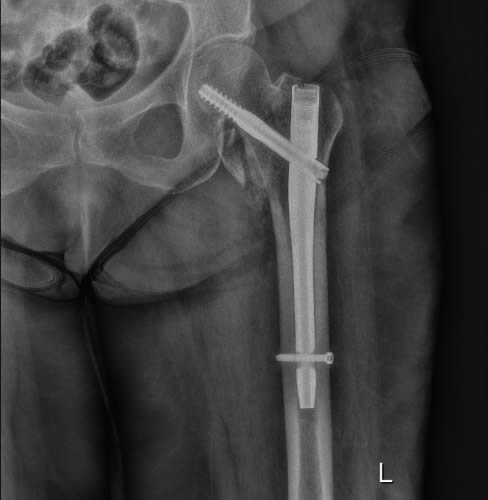

Οι ακτινογραφίες πραγματοποιούνται με πλήρως ψηφιακό εξοπλισμό και όχι ψηφιοποιημενο από έμπειρους Τεχνολόγους – Ακτινολόγους με άδεια ασκήσεως Επαγγέλματος.

Ο πιο σύγχρονος φορητός Ακτινολογικός εξοπλισμός πλήρως ψηφιακής απεικόνισης (DR) σε μια κινητή ακτινολογική μονάδα, μπορεί να επισκεφθεί τον ασθενή οπουδήποτε στην περιοχή της Θεσσαλονίκης και των περιχώρων και να σταλεί, αν ο ασθενής το επιθυμεί, η γνωματευμένη ακτινογραφία ηλεκτρονικά μέσω διαδικτύου στον θεράποντα- παραπέμποντα ιατρό ο οποίος θα λάβει το αποτέλεσμα στο προσωπικό του υπολογιστή, tablet, Smartphone οπουδήποτε κι αν βρίσκεται.